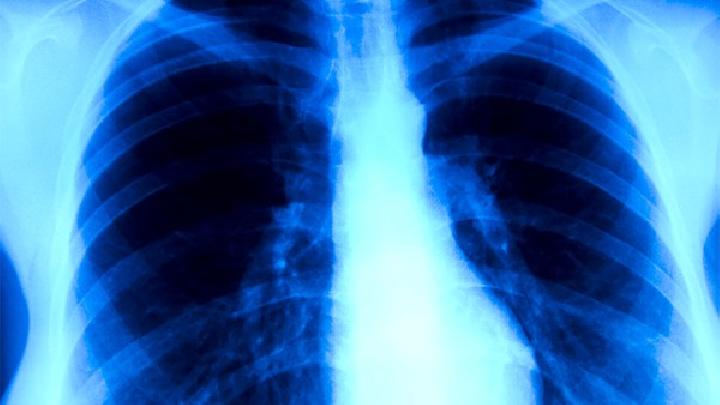

②病毒感染导致间质性肺炎,容易演变为慢性肺炎。首都儿科研究所病后有103例腺病毒肺炎1~5年随访,发现30.1%在X线路检查显示慢性肺炎和肺不张,个别儿童有支气管扩张。13例麻疹并发腺病毒肺炎2~3年度随访,其中6例已成为慢性肺炎。

炎症性病变可侵入各级支气管、肺泡、间质组织和血管。特别是在间质组织的炎症中,每次发作都有进展,破坏支气管壁的弹性纤维,最终由于纤维化而导致管腔狭窄。同时,由于分泌物堵塞管腔,肺不张,最终导致支气管扩张。

由于支气管壁和肺泡壁的破坏,空气通过淋巴管扩散,进入组织间隙,间质性肺气肿。局部血管和淋巴管也发生增生性炎症,管壁增厚,管腔狭窄。